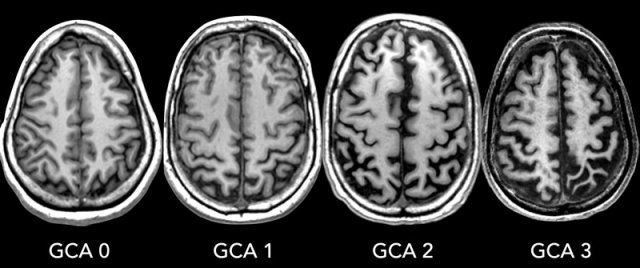

Fazekas scale for WM lesions

On MR, white matter hyperintensities (WMH) and lacunes - both of which are frequently observed in the elderly - are generally viewed as evidence of small vessel disease.

The Fazekas-scale provides an overall impression of the presence of WMH in the entire brain.

It is best scored on transverse FLAIR or T2-weighted images.

Score:

• Fazekas 0: None or a single punctate WMH lesion

• Fazekas 1: Multiple punctate lesions

• Fazekas 2: Beginning confluency of lesions (bridging)

• Fazekas 3: Large confluent lesions

Fazekas 1 is considered normal in the elderly.

Fazekas 2 and 3 are pathologic, but may be seen in normally functioning individuals.

They are however, at high risk for disability.

In 600 normally functioning elderly people the Fazekas score predicted disability within one year (table). In the Fazekas 3 group 25% was disabled within one year (10).

Three year follow-up shows that severe white matter changes independently and strongly predict rapid global functional decline (17).